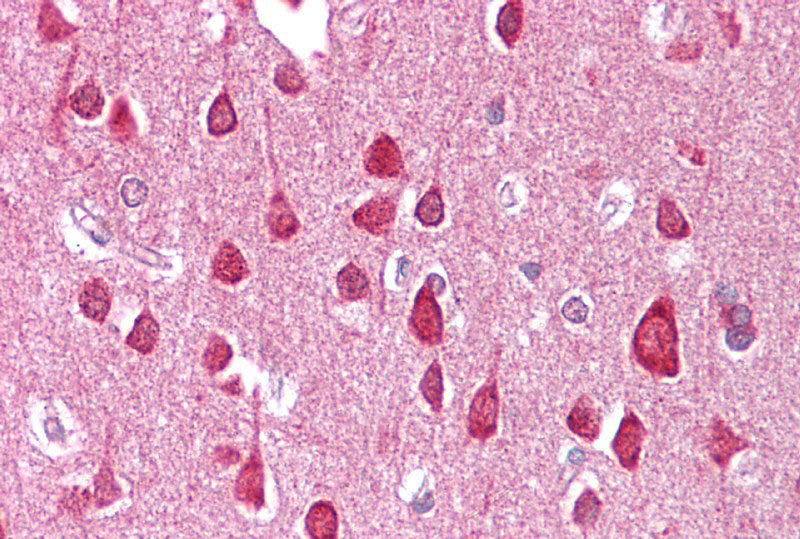

Immunohistochemistry with Brain, cortex tissue at an antibody concentration of 2.5μg/ml using anti-SLC18A1 antibody (APR13347G)

Brain, cortex